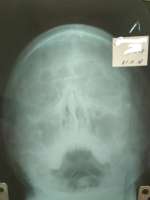

Друзья, поясните пожалуйста за рентген? Лор сказал, что это ринит, но не может же ринит уже 9 ЛЕТ! мучать мой носик?

>>799841

Что-то обе верхнечелюстные и левая лобная пазуха выглядят хреновато. И перегородка чуть кривая

Аноним 09/11/18 Птн 08:03:15 799867180

>>799866

Либо лобной вообще нет, непонятно

Аноним 09/11/18 Птн 08:08:23 799870181

>не может же ринит уже 9 ЛЕТ! мучать мой носик?

что же ему помешает?

Аноним 09/11/18 Птн 09:10:38 799880182